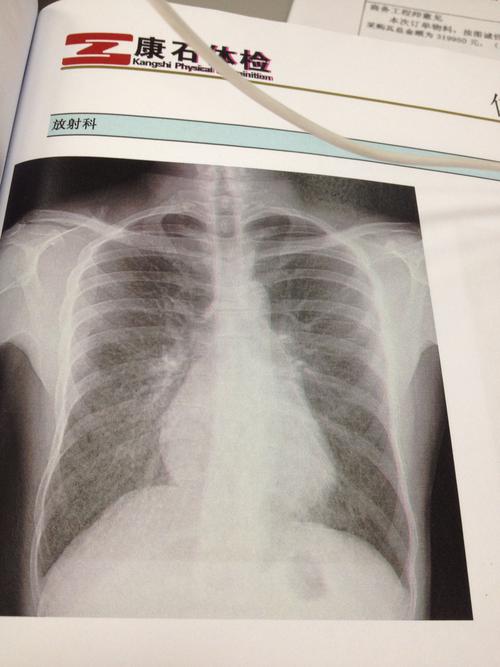

胸透正常的报告单图片

胸透报告单

胸透检查报告